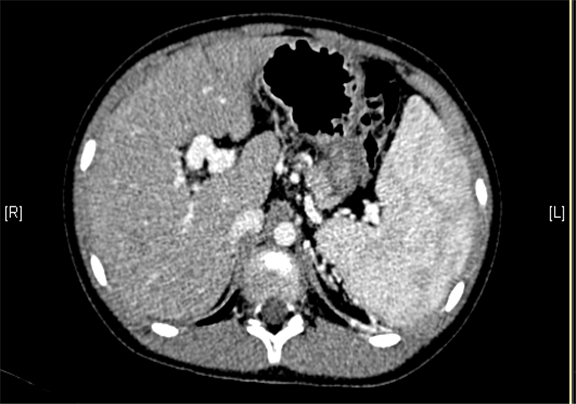

上腹部增强CT:门静脉主干走行迂曲、分支紊乱,考虑门静脉畸形可能性大,不除外门静脉海绵状变性。

术前CT检查:

动脉期